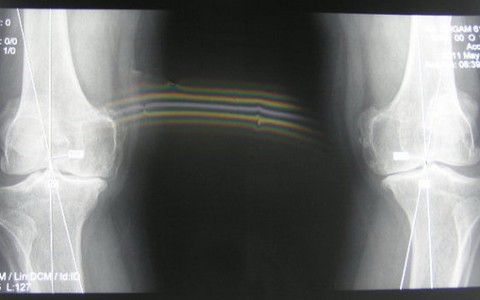

Khô khớp là hiện tượng các khớp khi vận động phát ra tiếng động lạo xạo hay lục khục. Đây là một triệu chứng của bệnh lý khớp.

TT - Đau khớp, khô khớp là căn bệnh rất thường gặp không chỉ ở người lớn tuổi. Nếu phải chịu đựng những cơn đau kéo dài như thế, chúng ta không nên xem thường mà cần gặp bác sĩ sớm để được định bệnh, kê toa.